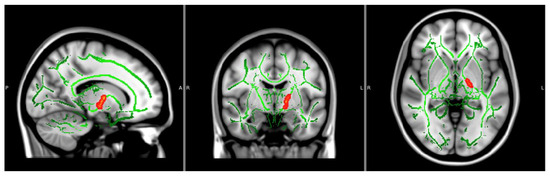

| FA Values | Voxels | MAX | MAX X (vox) | MAX Y (vox) | MAX Z (vox) |

| 22 | 0.95 | −23 | −19 | 2 | |

| OD Values | Voxels | MAX | MAX X (vox) | MAX Y (vox) | MAX Z (vox) |

| 39 | 0.958 | −16 | −11 | −5 | |

| 27 | 0.962 | −16 | −5 | 5 | |

| 17 | 0.956 | −21 | −16 | 1 |